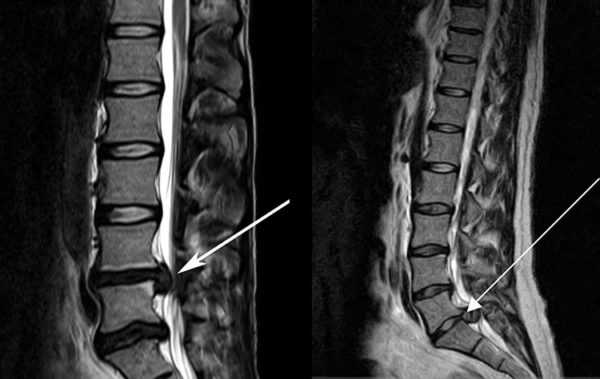

- Обязательна предварительная сдача всех необходимых анализов и прохождение обследований, таких как КТ и МРТ. Также консультироваться желательно не у одного врача, а у нескольких.

Грыжа межпозвонковых дисков на МРТ